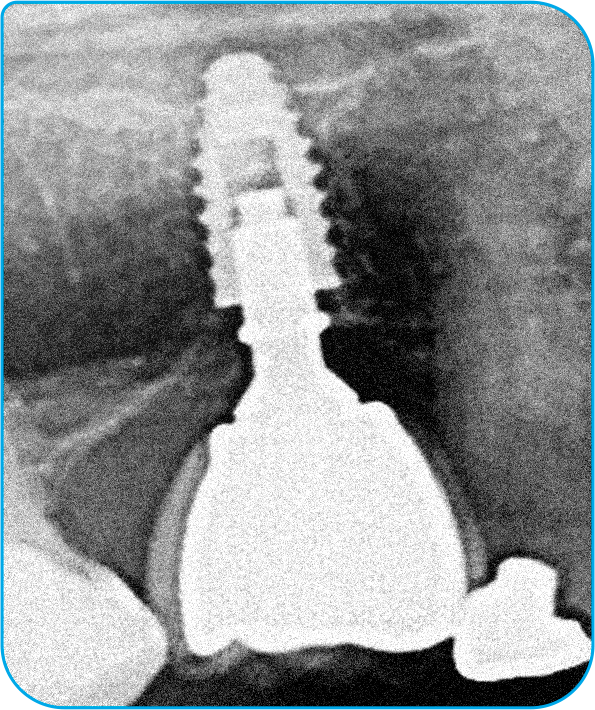

O caso clínico iniciou-se em 2015 com o objetivo de restaurar função e estética. Foram instalados dois implantes nas regiões dos dentes 35 e 36, seguidos pela osseointegração e condicionamento tecidual. As próteses finais foram confeccionadas sobre pilares Arcsys, com ajustes oclusais precisos. O acompanhamento clínico completa dez anos, com exames periódicos e manutenção regular. Observa-se excelente estabilidade óssea e saúde peri-implantar. O caso comprova que protocolos bem executados e componentes de qualidade garantem longevidade previsível.

1 | Imagem tomográfica (corte panorâmico) inicial.

2 | Imagem radiográfica após a instalação dos implantes e componentes protéticos.